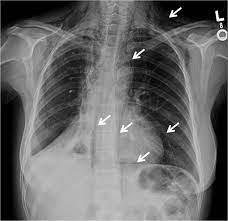

The Stages Of Pulmonary Sarcoidosis What Do They Really Mean Foundation For Sarcoidosis Research from www.stopsarcoidosis.org Emphysema does not, however, lead to lung cancer. In the united states, trends in lung cancer tend to follow trends in cigarette smoking. Lung cancer develops due to the overgrowth of. Chronic obstructive pulmonary disease (copd) is a serious lung condition found mostly in smokers. If the condition is misdiagnosed or its symptoms are ignored, a patient may not receive appropriate treatment until the cancer has progressed to an advanced stage. When sarcoidosis affects the lungs, symptoms can mimic idiopathic pulmonary fibrosis including shortness of breath and a dry cough. Pneumonia is a lung infection that leads to breathing difficulties and fluid in the lungs. Malignant tumors trigger inflammation in surrounding normal lung tissue, and they may obstruct your airways and interfere with normal airflow.

Stereotactic Body Radiation Therapy For Early Stage Non Small Cell Lung Cancer A Primer For Radiologists Radiographics from pubs.rsna.org Having copd may put you at risk for lung cancer and heart disease, among other conditions. This is because smoking complications can extend from lung tissue damage (emphysema) to lung cell damage (cancer). When cancer begins in the cells of the lung it is known as primary lung cancer. Various viruses, bacteria, and fungi can cause pneumonia. Lung cancer is a general term that includes all abnormal lung tissue cells that multiply unregulated and form tumors or growths in the lungs.these tumor cells may spread (metastasize) to other parts of the body.; In lung cancer, lung cells exhibit abnormal and uncontrolled growth starting the lungs, while asthma is caused by inflammation and/or mucus that decreases or blocks the breathing passages (bronchioles) of the lungs. Although slipping from emphysema to copd is usually not a drastic decline in health, early detection of lung cancer is critical for increasing your treatment options and improving your prognosis. Initial reports of an association between lung cancer and emphysema date back to the 1950s, when a report on 10 patients with congenital cystic pulmonary emphysema who died from primary lung cancer was published (4).